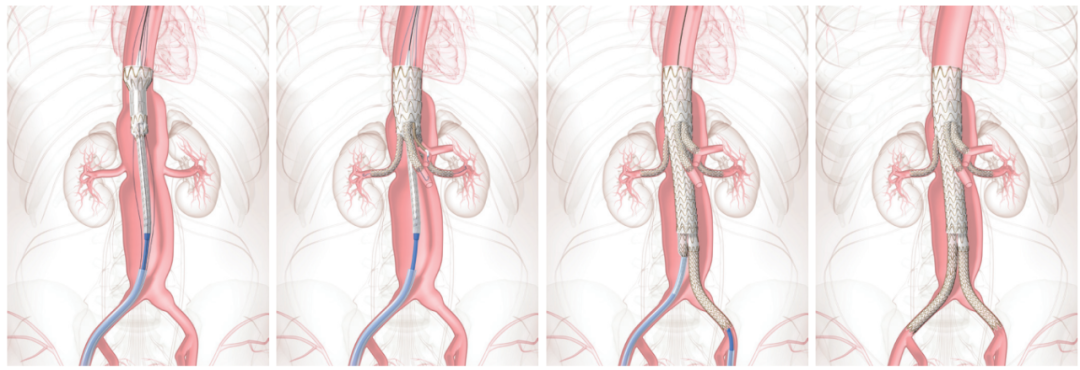

植入TAMBE的过程包括将不同的部分通过腿部的股动脉和上臂的肱动脉或腋动脉输送到主动脉。

使用透视或实时X射线图像植入部件,并按照以下步骤在监视器上查看(上图说明了这些步骤):

1. 主动脉部分通过股动脉插入并位于动脉瘤上方。然后对其进行部分展开。

2. 分支部分通过主动脉部分设计的开口插入和展开,并进入相应的内脏动脉。

3. 在主动脉部分完全展开后,插入并展开其他部分,如远端分叉部分和对侧腿部分,以完成主动脉支架贴附。

4. 一旦所有部分都展开,可以使用血管内球囊来帮助完全扩张和密封装置贴到血管壁。